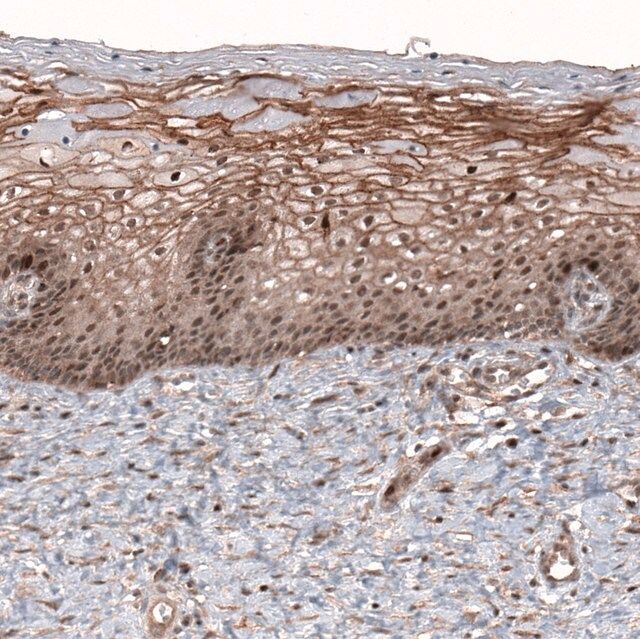

The gene LMO7 (LIM domain only protein 7) is mapped to human chromosome 13q22.2. LMO7 is expressed in early stages of muscle and heart development. The protein localizes in the nucleus and cytoplasm.

Anti-LMO7 antibody produced in rabbit, a Prestige Antibody, is developed and validated by the Human Protein Atlas (HPA) project (www.proteinatlas.org). Each antibody is tested by immunohistochemistry against hundreds of normal and disease tissues. These images can be viewed on the Human Protein Atlas (HPA) site by clicking on the Image Gallery link. The antibodies are also tested using immunofluorescence and western blotting. To view these protocols and other useful information about Prestige Antibodies and the HPA, visit sigma.com/prestige.

LMO7 (LIM domain only protein 7) is responsible for activation of myocardin-related transcription factors (MRTFs) and thereby regulates actin cytoskeleton and breast cancer cell migration. LMO7 is linked with Emery-Dreifuss muscular dystrophy.